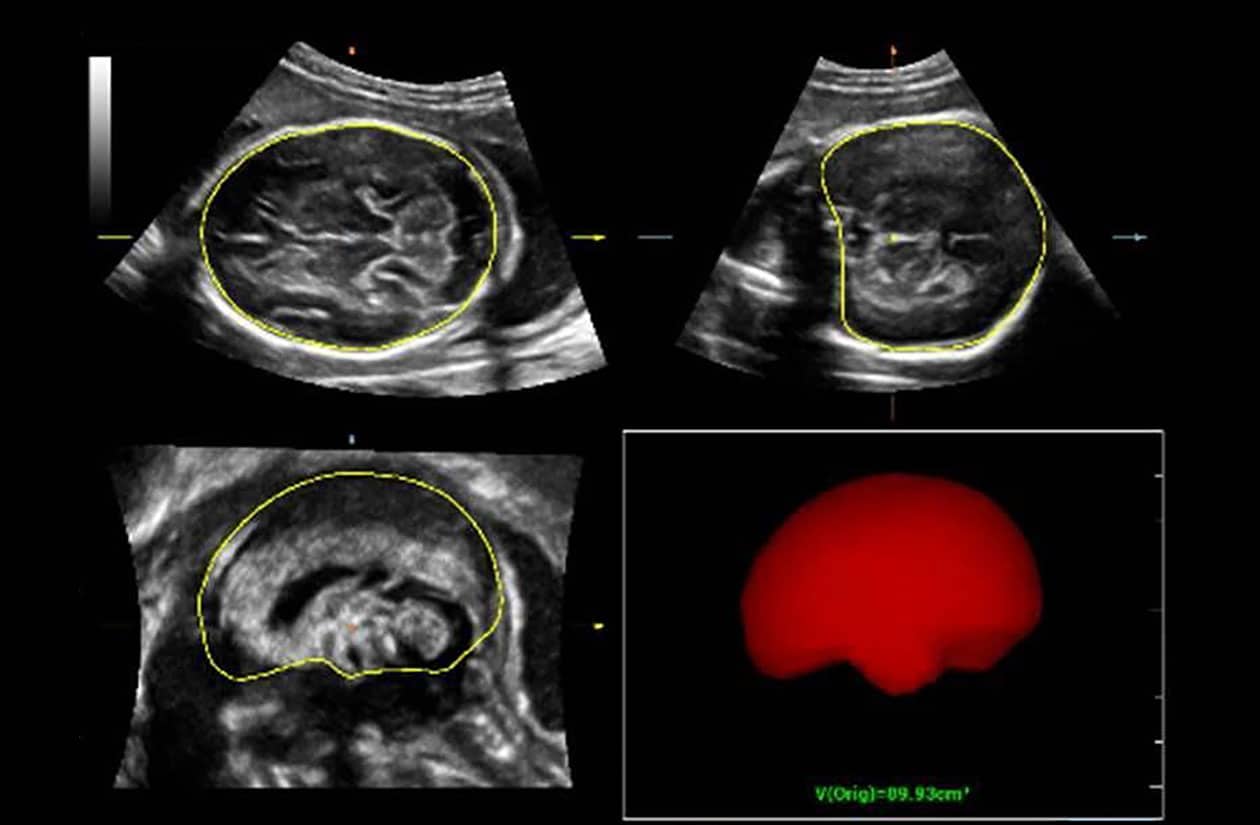

To address the changing needs of today’s value-based care environment, the Resona 7 Ultrasound System Platinum Edition was developed to capture clear, uniform images for radiology, vascular, women’s health, pediatric, and shared service imaging applications.

Premium imaging coupled with advanced workflow technologies help ease clinicians’ increasing workload by offering intuitive and easy-to-use smart tools and AI-enhanced technologies to elevate clinician and patient satisfaction. The user-directed ergonomic design is ideal for daily use, enabling clinicians to capture premium images without sacrificing comfort.